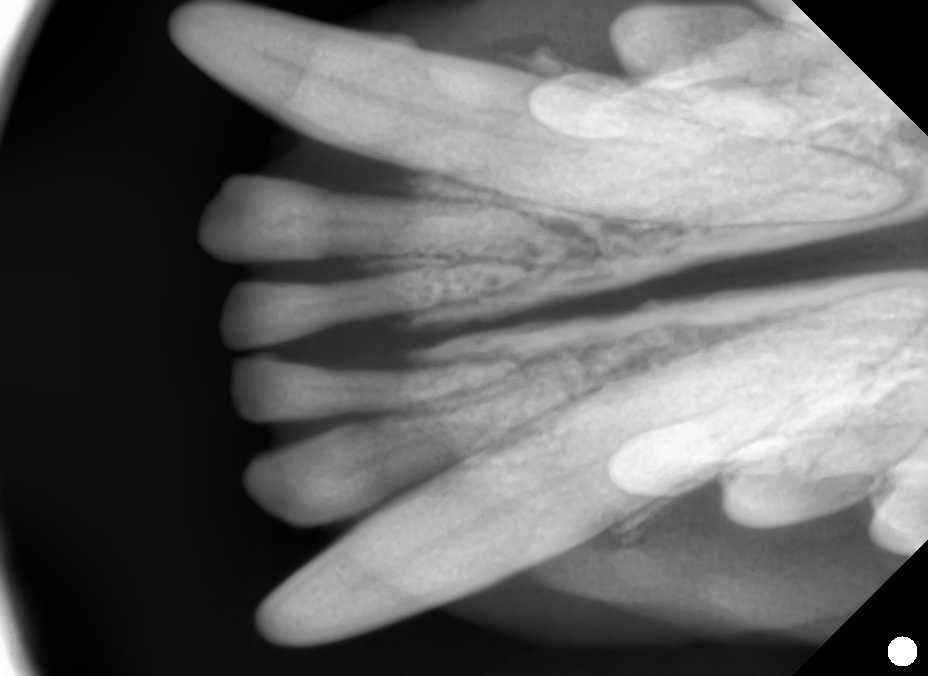

今回の症例

下顎切歯が左右2本ずつ(計4本)しかないトイプードルが来院しました。

外見上は単なる欠如歯に見えましたが、歯科用レントゲンを撮影したところ、萌出していない埋伏歯はなしと判明。

この結果、先天欠如歯と診断しました。

診断には歯科レントゲンが必須

欠如歯と埋伏歯は、口を見ただけでは確実な判断はできません。

特に小型犬では、レントゲンで歯胚の有無を確認することが重要です。